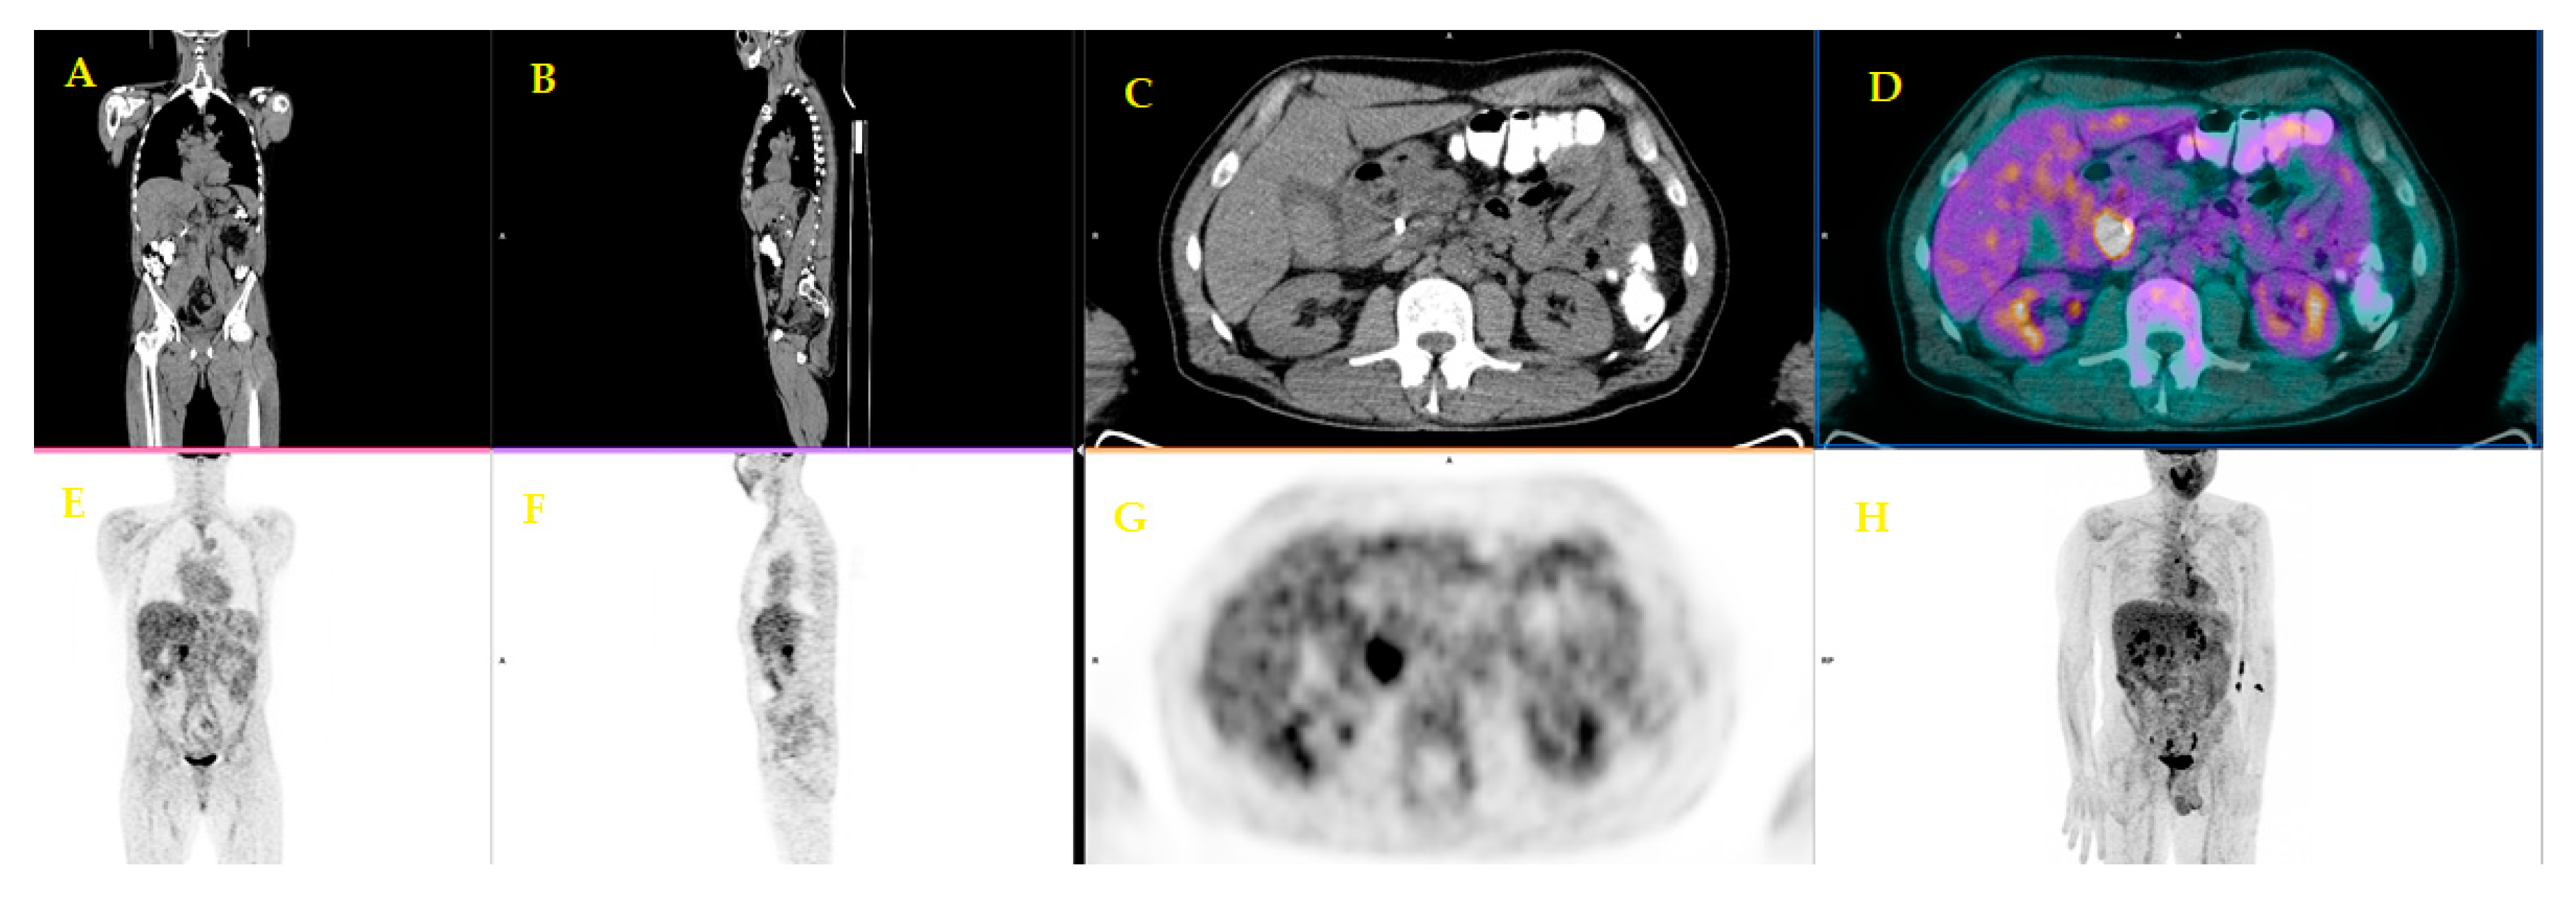

| 9 | Picchio et al. [24] | 2012 | Prospective study | 42 | Patients selection for helical tomotherapy with concurrent chemotherapy | PET/CT influenced the treatment strategy by detecting distant metastases not documented by CT, thus accurately selecting patients for hormonal-chemotherapy after induction chemotherapy |